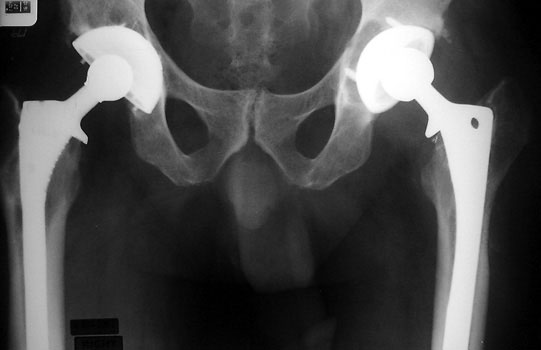

Acetabular Component Anteversion

• Cup should be anteverted 15 +/- 10 degrees.

• Anteversion is difficult to accurately evaluate on radiographs, and can only be qualitatively assessed on a groin lateral view. This view is difficult to obtain, especially in the elderly or post operative patient, and is effected by pelvic or thigh rotation.

• CT is the imaging modality of choice to evaluate for anteversion

The right cup is normally anteverted, the left cup anterior and posterior rims are far apart, suggesting excessive anteversion.

R

L

Groin lateral films: R cup normal anteversion, L cup excessive anteversion